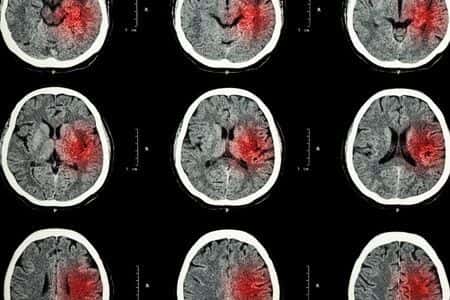

This case takes place in Washington and involves a male patient who presented to the ER with complaints of neck pain and nausea. He underwent multiple scans and diagnostic tests, all of which appeared to be negative for major injuries or potential causes for his symptoms. As a result of these findings, the patient was prescribed painkillers and instructed to return if his symptoms became worse. Several days later, the patient presented to the ER again with complaints of increased neck pain, as well as continuing nausea. His treating physicians discharged him again after prescribing a higher dose of painkillers. A few days later, the patient was rushed to a different hospital after being found unconscious on his kitchen floor. A new round of scans were performed which revealed the presence of a significant hemorrhage in his brain, at which point the patient was admitted for emergency surgery. It is alleged that the initial scans were not reviewed correctly, and that the patient should have received appropriate treatment much sooner.